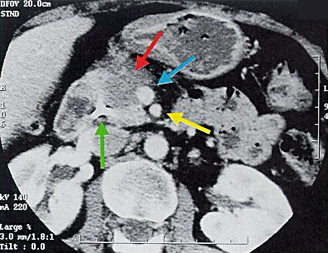

Pancreatic head adenocarcinoma